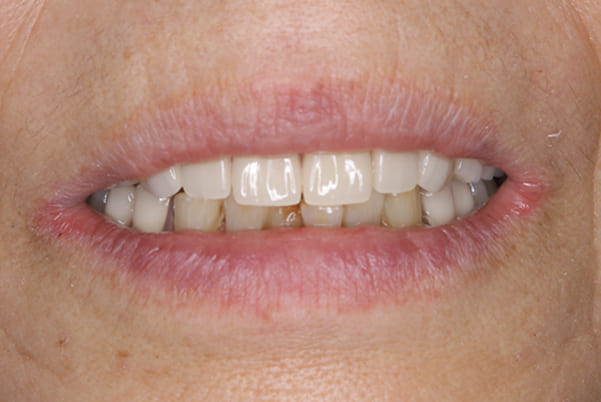

精密義歯は、歯をぬいたあと歯肉が治ってから、精密な入れ歯を作製しました。治療中も、仮の入れ歯があるため、普段の生活に支障がなく、また仮の入れ歯を実際使ってのご意見、ご希望(バネが気になる)をお聞きした上で、精密な義歯に、ご希望を反映し作製しました。

従来の方法では、歯を抜いてから入れ歯を作るまでは、歯茎の治りを待つため数か月かかりますが、患者様のご希望で、見た目、食べることに支障が出ないよう、抜歯と同時に入れ歯を装着し、歯がない期間がない入れ歯を作製したため、その日から、お食事や外出が可能となりました。

また、当然ではありますが、患者様も残りの歯をこれ以上失いたくないとのご希望が強く可能な限り、残りの歯に負担がかからない機能性を重視し、また、バネがなるべく見えない設計とし、機能と審美の両方に重きをおいた入れ歯を作製し、お痛みなく、お食事も召し上がられるようになりました。

左上に入れ歯を装着されていますが、金属のバネがなく自然な口元に